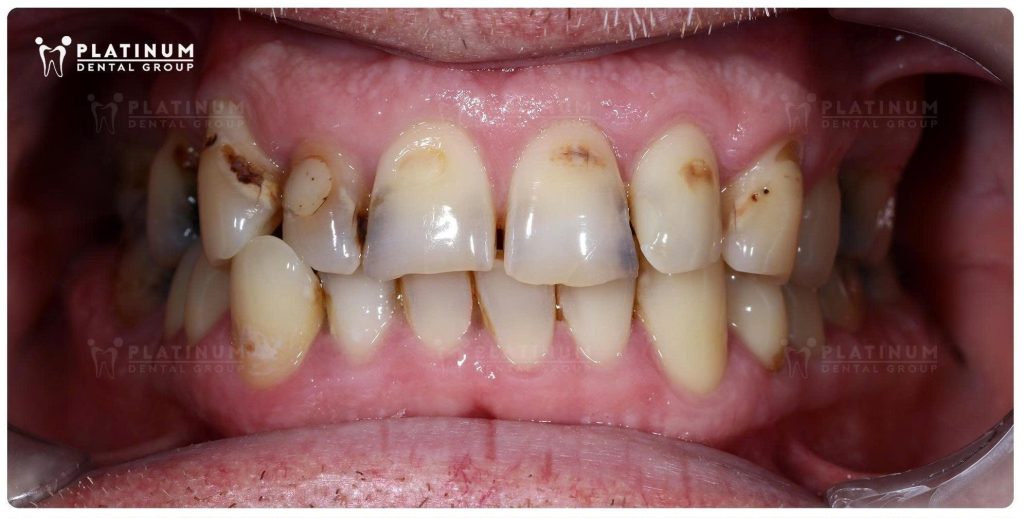

For a long time, he had been living with missing back teeth, while several of his remaining teeth were badly decayed and fractured. Over time, this affected far more than just the appearance of his smile. His chewing function had become seriously compromised, meals were no longer enjoyable, and his confidence had gradually faded.

His treatment included:

Restored the heavily damaged teeth with porcelain crowns and refined the smile line for a more balanced appearance.